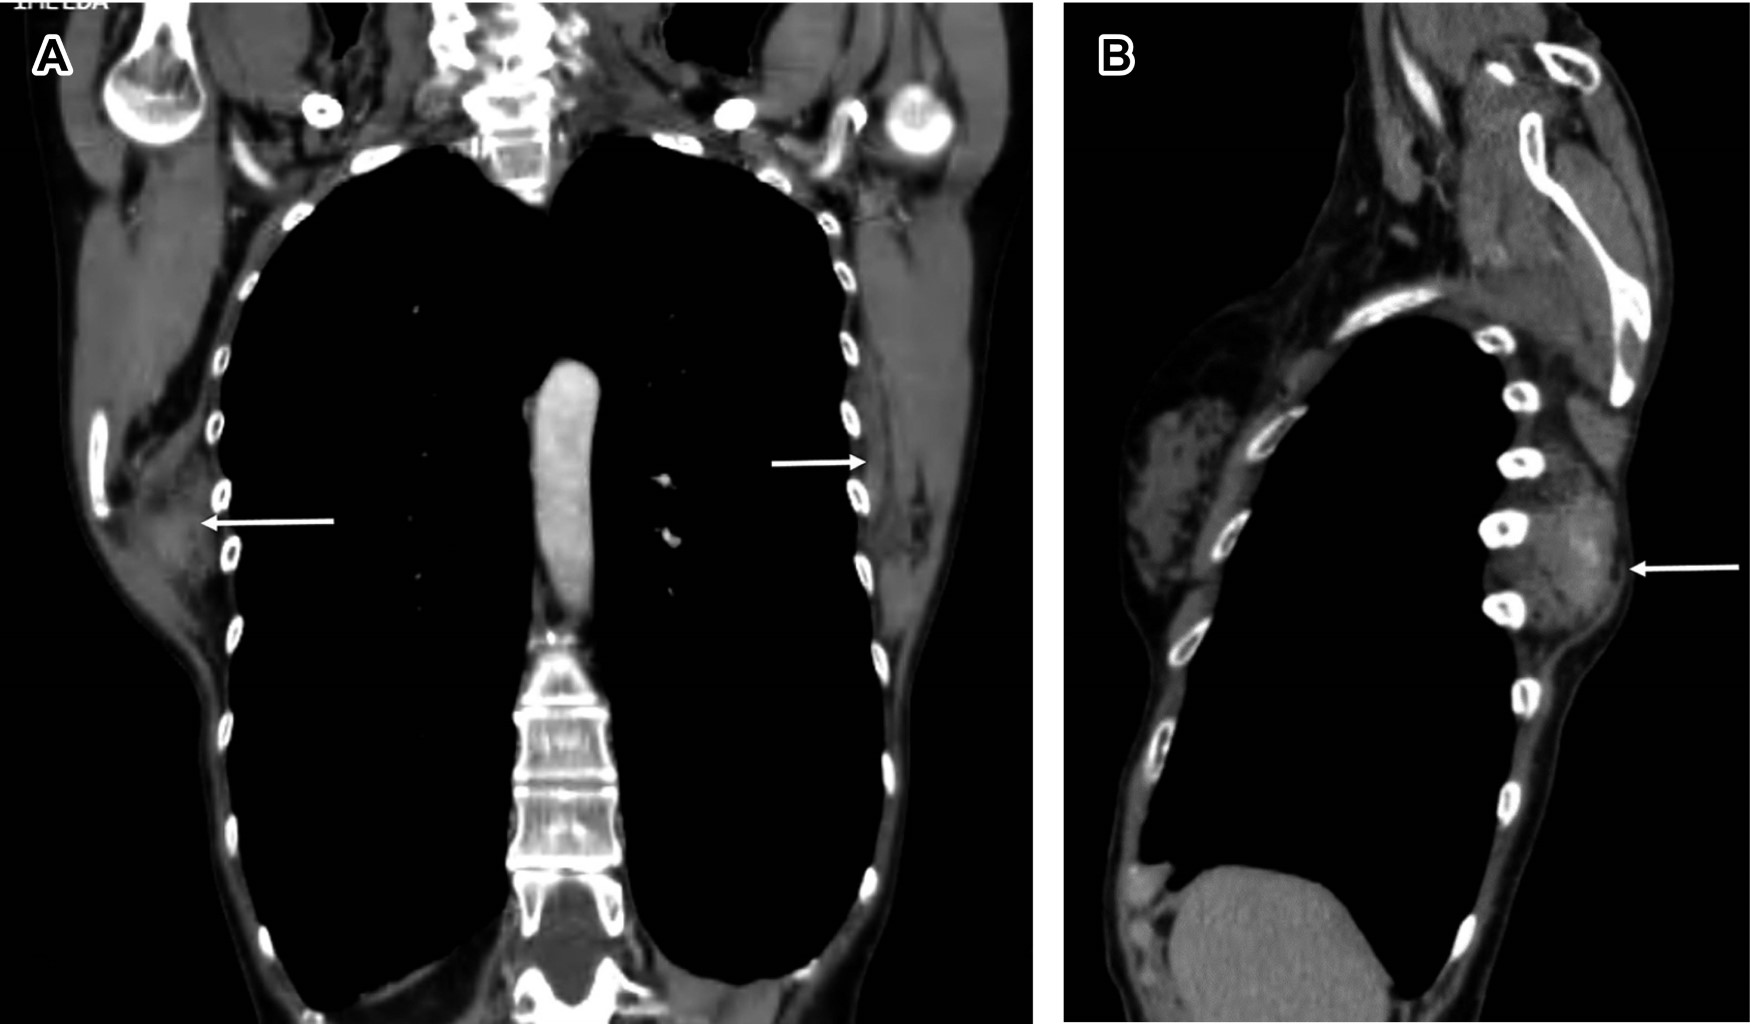

Paciente femenino de 60 años, ama de casa, acude por presentar abultamiento de cinco años de evolución en región escapular derecha, que le ocasiona discreta molestia al efectuar limpieza en el hogar. A la exploración se observa masa de consistencia ahulada en ángulo inferior de escápula derecha prominente, con dimensiones de 7 × 5 cm (Figura 1A-C), no dolorosa al movimiento, con sensación de frote a los desplazamientos de ambas escápulas, con arcos de movilidad de hombros completos y sensibilidad normal; el resto de la exploración es normal. Con diagnóstico presuntivo de elastofibroma dorsi. Se solicita tomografía computarizada (Figuras 1, 2 y 3) que confirma elastofibromas dorsi bilaterales; se propone cirugía, la cual rechaza.

La ecografía, la tomografía computarizada y la resonancia magnética confirman el diagnóstico.4 En la ecografía se observa un patrón alternante, de tipo fasciculado o laminar, de líneas hipo e hiperecogénicas paralelas a la pared torácica; la señal Doppler suele ser negativa. La TC muestra alternancia de tejido adiposo con densidad grasa y de tejido fibroso con densidad muscular, que no realza con medios de contraste. La resonancia magnética es de elección para llegar al diagnóstico presentando patrón alternante de tejido adiposo y fibroso; en T1 y T2 el tejido fibroso da señales de baja intensidad similares a las del músculo. El tejido adiposo da señales de alta intensidad en T1 y señales intermedias en T2. La biopsia se reserva para los casos sospechosos que no presentan el patrón característico.5